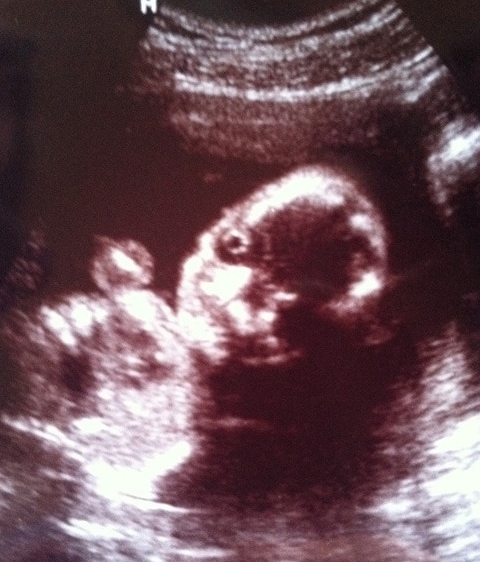

▲터미네이터 태아 ⓒ 온라인 커뮤니티

사진은 아기의 모습을 촬영한 초음파 사진. 태아의 크고 둥근 눈이 마치 인공 눈 같고 특히 주먹을 꽉 쥔 것 같은 손 모양까지 더해져 말 그대로 ‘터미네이터 태아’같은 무시무시한 분위기를 연출한다.

한편 사진을 접한 누리꾼들은 "터미네이터 태아, 정말 그럴싸하다", "만약 진짜면 왠지 무서울 듯" 등의 다양한 반응을 보였다.